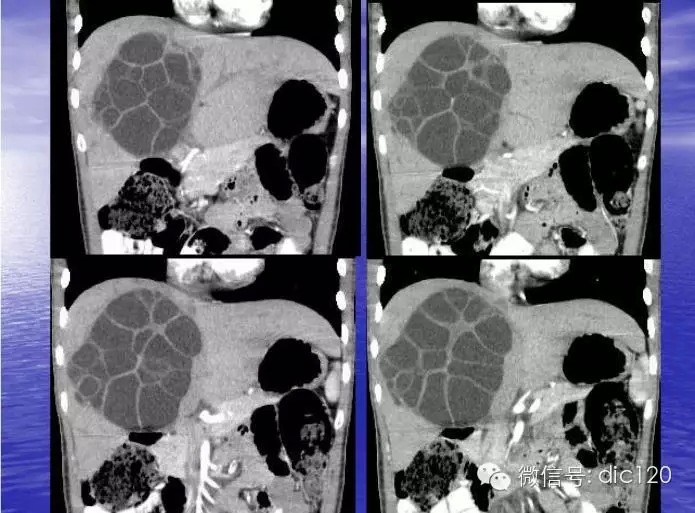

肝包虫病CT表现:

(1)肝内圆形或类圆形低密度区,CT值可在-14~25HU,密度均匀一致,增强后无强化表现。边界清楚,光整。囊壁及囊内分隔有增强效应。

(2)大的囊腔内可见分房结构或子囊(囊内囊)。子囊的数目和大小不一。如子囊主要分布在母囊的周边部分呈车轮状。

(3)囊壁可见钙化,呈壳状或环状,厚薄可以规则,为肝包虫病特征性表现。

(4)因感染或损伤,可造成内囊分离,如内、外囊部分分离表现为双边征;如内囊完全分离、塌陷、卷缩,并悬浮于囊叶中,呈水上荷花征。偶尔完全分离脱落的内囊散开呈飘带状阴影。

肝包虫病是牧区较常见的寄生虫,也称肝棘球蚴病。在中国主要流行于畜牧业发达的新疆、青海、宁夏、甘肃、内蒙和西藏等省区。病因犬绦虫寄生在狗的小肠内,随粪便排出的虫卵常粘附在狗、羊的毛上,人吞食被虫卵污染的食物后,即被感染。虫卵经肠内消化液作用,蚴脱壳而出,穿过肠黏膜,进入门静脉系统,大部分被阻留于肝脏内。蚴在体内经3周,便发育为包虫囊。包虫囊肿在肝内逐渐长大,依所在部位引起邻近脏器的压迫症状,并可发生感染,破裂播散及空腔脏器阻塞等并发症。